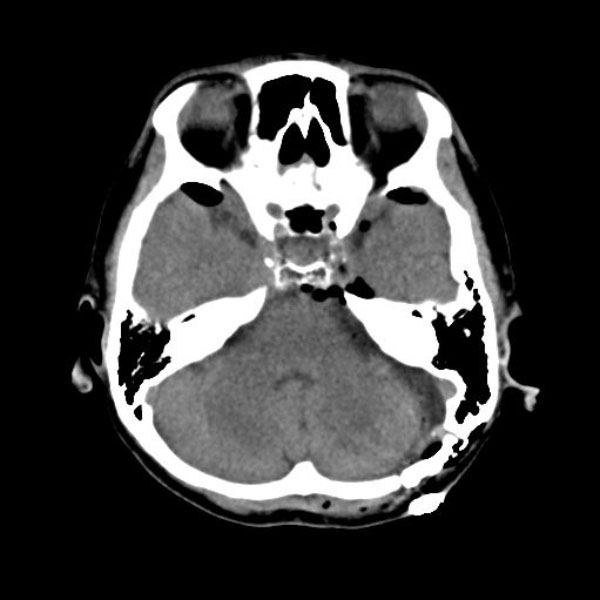

手術後

(CT)